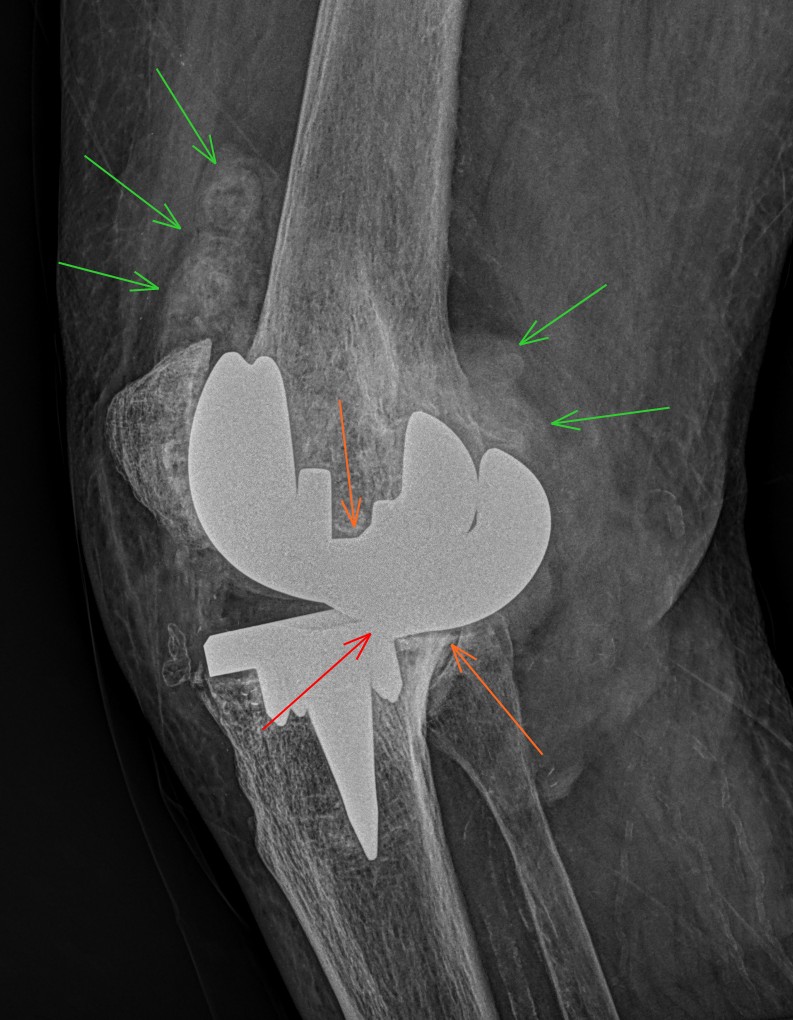

JuanMiranda@themskarchive·

3/10/2025.🦴⚠️69yo male, h/o bilateral TKA, c/o R knee pain. XR (Right knee): 🟥 Loss of polyethylene + metal-on-metal contact 🟨 Prosthesis loosening 🟩 Capsular distension w/ metallic debris ✅ Left knee: normal ❌ Right knee: advanced metallosis #Metallosis #Radiology #TKA

JuanMiranda tweet media